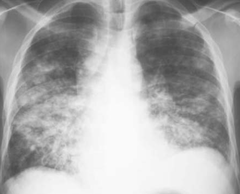

Pneumoconiosis

Inhalation and retention of dust (Assocated with pulmonary fibrosis (radiograph) and tumors